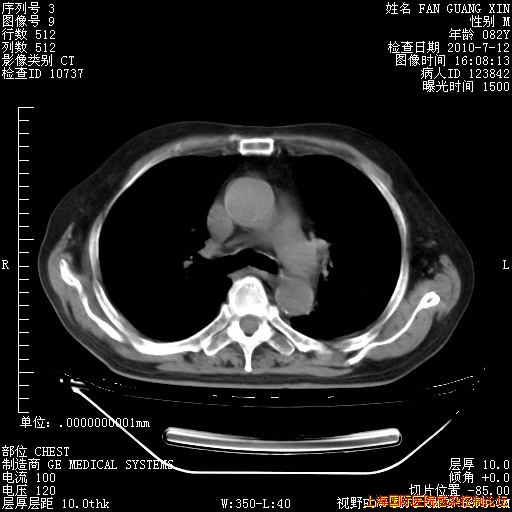

今天复查CT